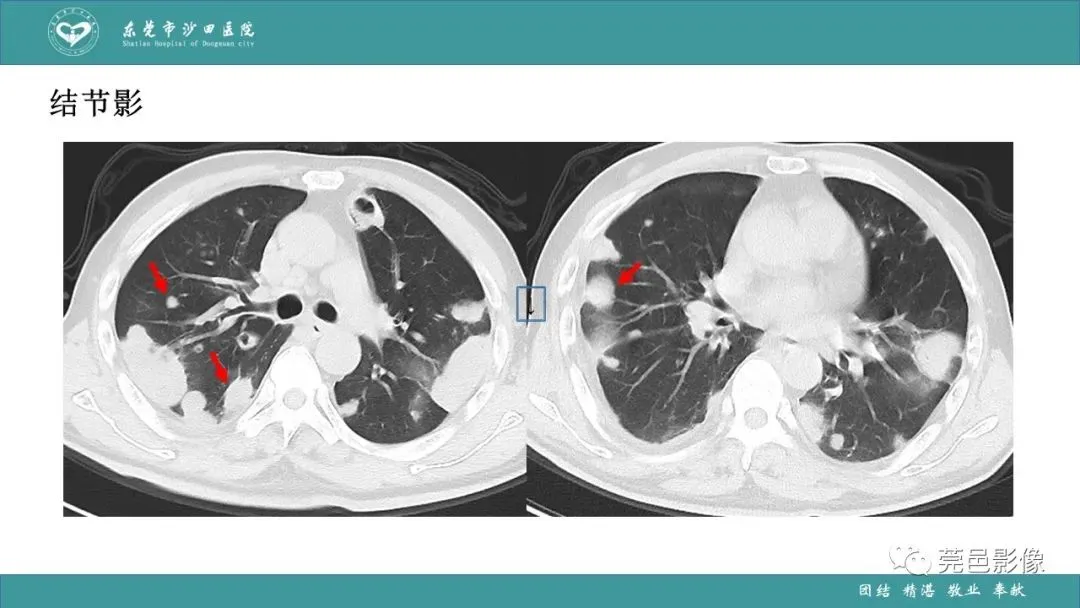

>课件 | 肺炎克雷伯杆菌肺炎影像学诊断与鉴别诊断

课件 | 肺炎克雷伯杆菌肺炎影像学诊断与鉴别诊断